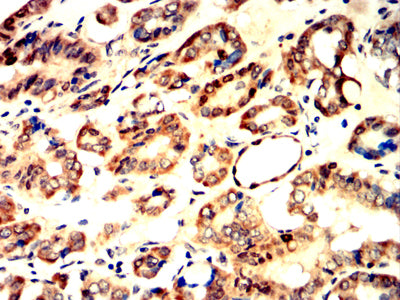

分类: 科研抗体货号: 32355别名: CAT3; ATRC3; CAT-3应用: WB,IHC,FCM反应种属: Human, Mouse, Rat